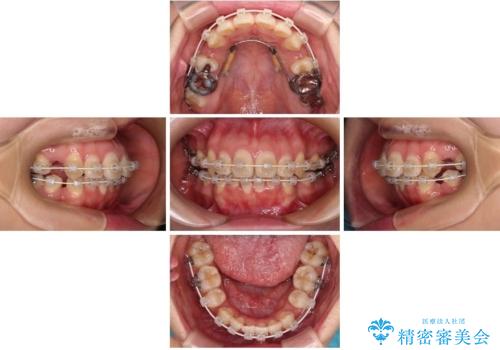

- 下の前歯のデコボコと、口元の突出感を改善したいと来院された患者様です。

突出感の強い上顎前歯をしっかりと後方移動させるため、上顎の裏側の補助装置(リンガルアーチ)とアンカースクリューを併用しています。

上下左右の第一小臼歯を抜歯して、目立ちにくいワイヤー装置で矯正を行いました。